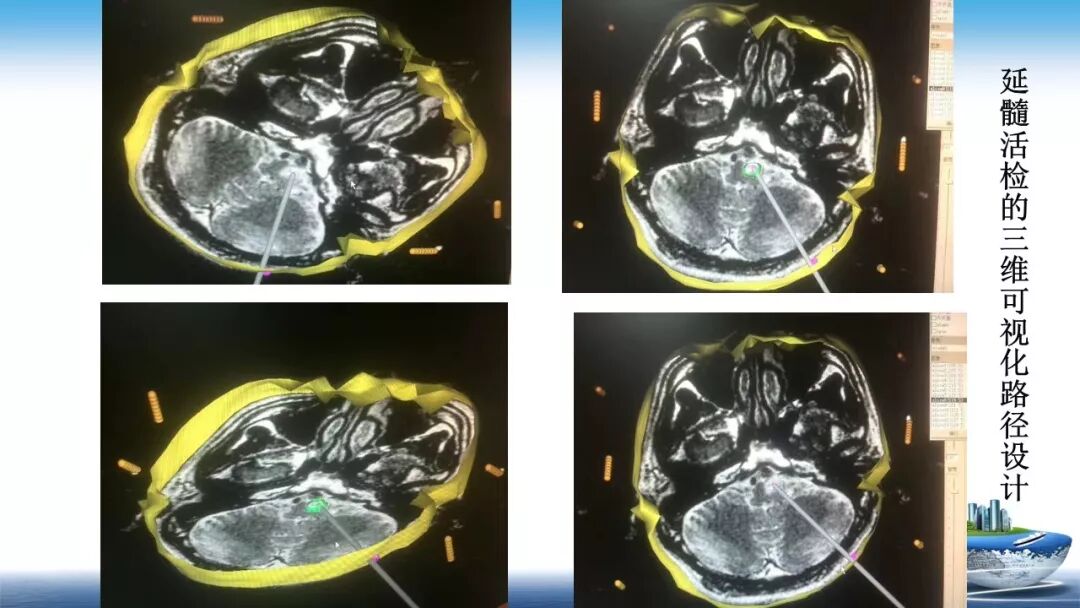

立体定向活检在脑干中线病变精准诊断中的作用

今天为大家带来的是中国人民解放军总医院第六医学中心(原中国人民解放军海军总医院)王亚明、于新、张剑宁带来的精彩课题分享:立体定向活检在脑干中线病变精准诊断中的作用,欢迎观看、阅读!